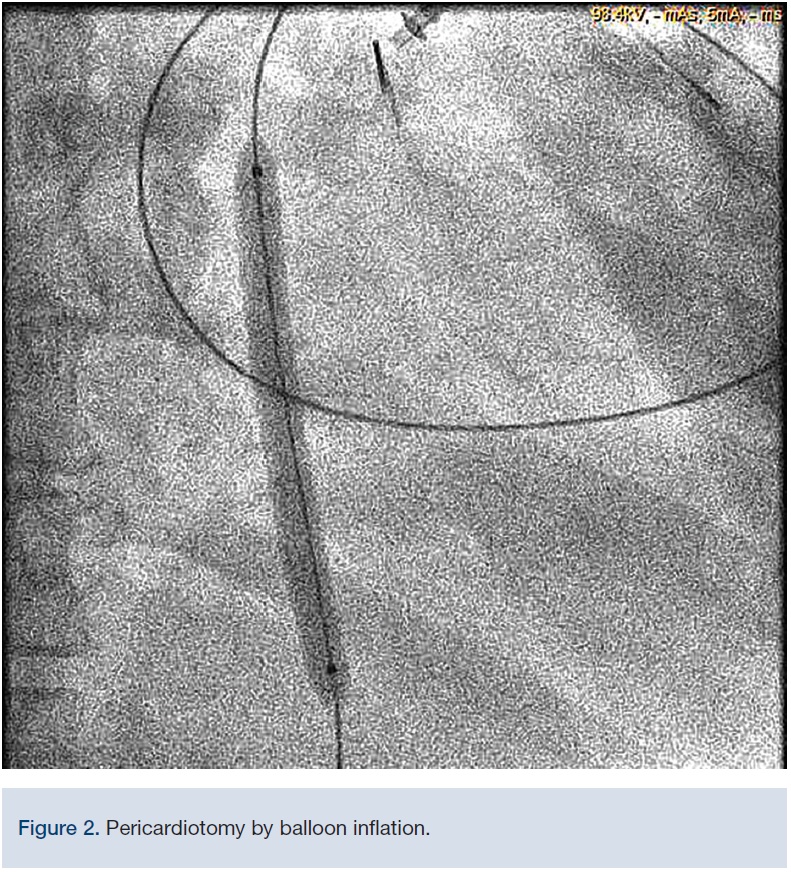

Procedure: A spinal needle was introduced under the xiphoid process, and directed posteriorly toward the tip of the left scapula until the pericardial space was entered and fluid aspirated. Bloody pericardial fluid was aspirated. Echo was used to confirm positioning. A long exchange wire was introduced via fluoroscopy and was shown to loop around the heart, confirming location in the pericardial space. A fenestrated pigtail catheter was introduced into the pericardial space over a guidewire and fluid collection was started, using the provided 50 ml syringe. After draining fluid, we exchanged the pigtail catheter for an over-the-wire 5.0 x 40 mm Admiral Xtreme balloon (Medtronic) to perform pericardectomy, followed by a 7.0 x 80 mm Admiral Xtreme balloon (Figure 2) without any complications. A post-procedure echo was performed with substantial reduction in pericardial fluid. Approximately 900 mL of blood-tinged pericardial fluid was aspirated into a collecting bag.